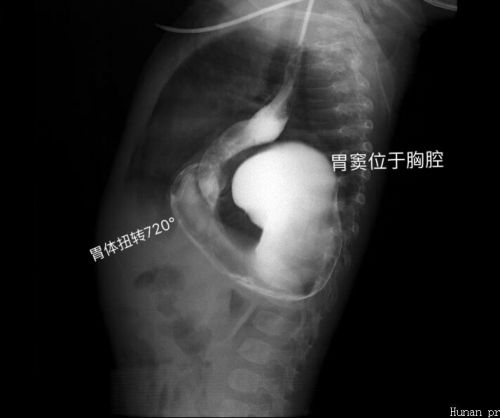

2019年1月19日,9个月大的男婴忱忱(化名)因呕吐4天、加重2天,急诊入住我院儿童医学中心。忱忱生下来一切正常,生长发育也很好,母乳喂养,6月按时添加辅食。可就在入院前4天,无明显诱因开始出现呕吐食物,并逐渐加重,呕吐咖啡色液体,并解黑色大便1次。入院后考虑为消化道梗阻,经过一系列检查,确诊为:巨大食管裂孔疝并胃扭转。

食管裂孔疝是一种先天性发育异常,较为罕见,表现为膈食管裂孔扩大,膈肌脚薄弱,腹段食管、胃等腹腔内脏器在腹压增高时经食道裂孔进入纵隔,使胃内容物向食管反流,病程较长还可以出现反复呼吸道感染的症状。食道裂孔疝合并消化道梗阻或者反复呼吸道感染的,一般都需手术治疗修复。患儿忱忱不仅全部胃体进入胸腔并且扭转,就连大肠也卡在胸腔,也叫“胸腔胃”,这便是导致忱忱进食后呕吐、不解大便的罪魁祸首。